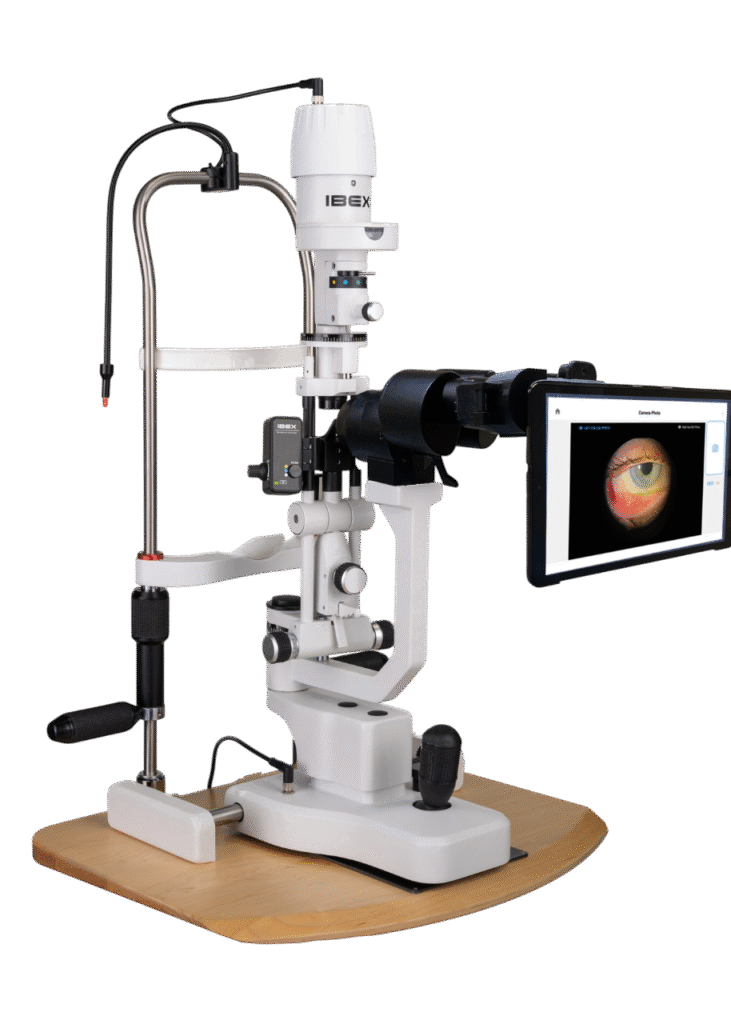

Opteon™ Slit Lamp Imaging + Meibography

Photos & Videos. Clinical Documentation. Patient Education. Reimbursement.

Illuminate your exams and transform patient engagement like never before. When patients see detailed images of their eyes, they gain a deeper understanding of their health and recognize the importance of compliance and follow-up care. Throughout development, our team saw firsthand the profound impact of imaging in the clinic—watching patients smile, express genuine appreciation, and embrace their health journey. That unforgettable experience remains the most rewarding part of our work.

Opteon was born and developed in the clinic, meticulously tested, and perfected through countless hours to ensure that it flows with your exam routine — delivering unmatched reliability and efficiency.

Pushing ahead, our imaging system includes our new, patent-pending Halo background light. Working with native slit lamp illumination, Halo delivers unparalleled clarity of the ocular adnexa. You’ll uncover details of the meibomian glands, acinar spaces, conjunctiva, lid margins, and lashes like never before.